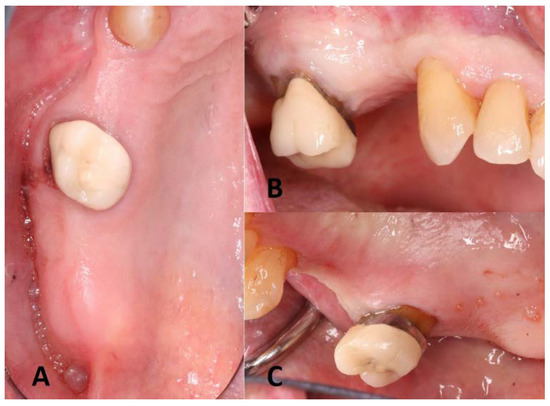

3. Surgical Procedures